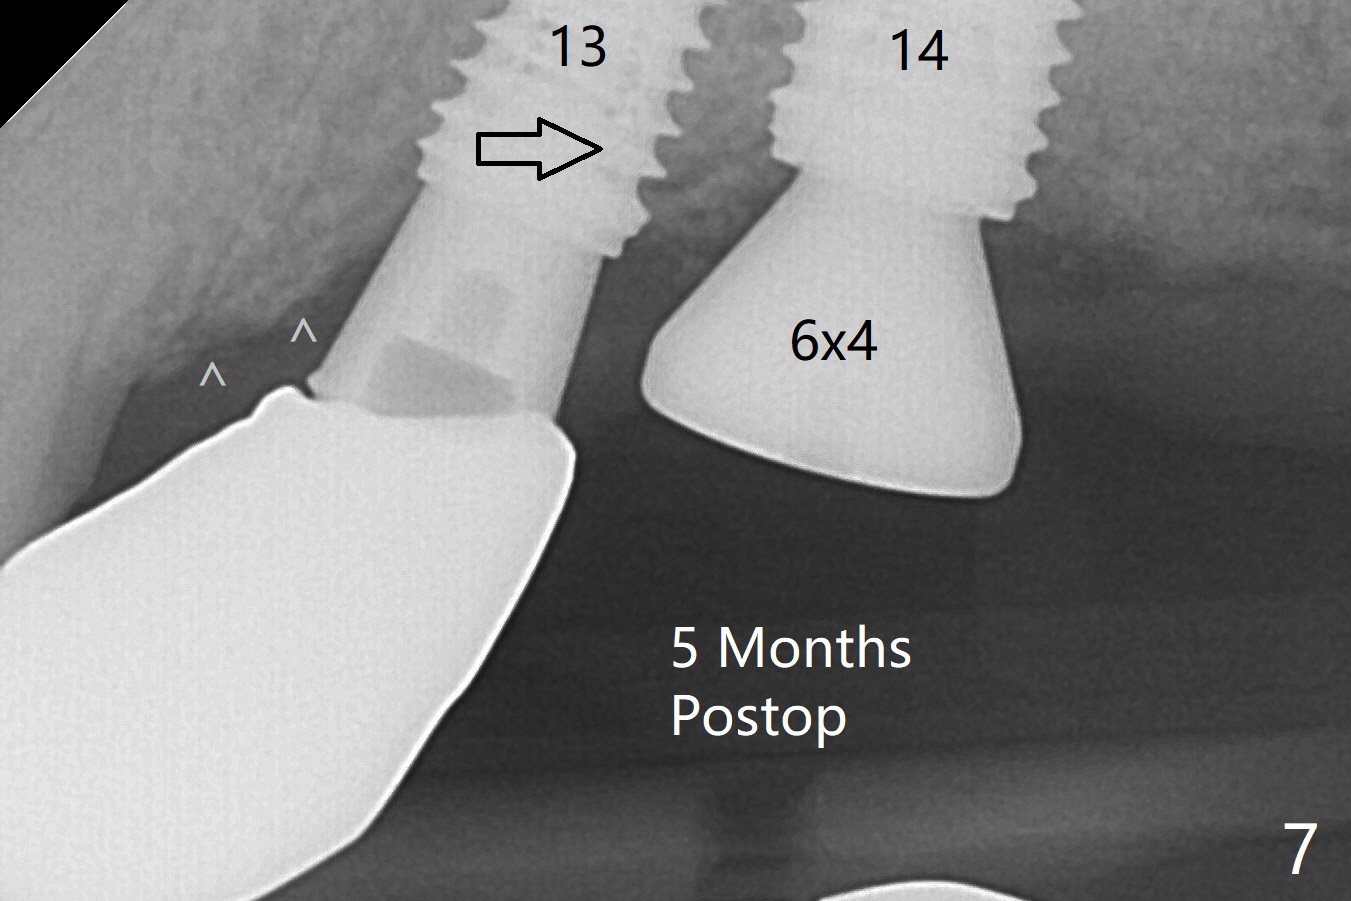

Three months post #14 implant removal and bone graft, the existing guide is reused, but no stop fixture mount cannot be inserted into #13 implant as an anchor. After 3.5x7.3 mm drill with 12 mm offset, the bottom of the osteotomy is not so hard; therefore sinus lift is conducted with allograft and 4x10 mm dummy implant (Fig.1). The lifted sinus floor is in fact not noted during the surgery (Fig.1 dashed red line). Sinus lift continues with bone graft and 4.5x10 mm (Fig.2); bone graft is squeezed out (*). The final implant (5x8.5 mm) is not seated until use of 4.5x7.3 and 4.0x10 mm drills (Fig.3). The implant is further placed free hand until subcrestal distal; since the torque is not high, a healing screw (S) is placed with packing allograft around the plateau of the implant (*). By placing a 4.5x4.5(4) mm cemented abutment at #13, a provisional is fabricated with extension to cover the bone graft at #14. When the provisional dislodges 1.5 months postop, #14 wound does not heal with the erythematous gingiva and exposed healing screw (Fig.5). Diabetes is not well controlled (HbA1c >6% (normal 4-5.6%)). Poor oral hygiene is another contributing factor in failure. After cleaning and torque 30 Ncm of the abutment at #13, impression is taken. In fact the tooth #12 has lost the palatal cusp (Fig.6 <); a crown will be fabricated at #12 when the implant at #14 osteointegrates. The implant at #14 is uncovered 5 months postop (Fig.7 (6.8x3 mm healing abutment)). The implants of #13 and 14 are close to each other, which is related to the slanted ridge at #13 (^). The osteotomy and the implant slide distal during placement (arrow). The implant in the slanted ridge should be intentionally placed mesial to compensate for the shifting. Or the ridge should be trimmed precisely; open surgery is necessary. A 5.2x5.5(4) mm cemented abutment is apparently completely seated with 35 Ncm torque 6 months postop (Fig.8). Although the distal plateau of the implant is exposed when the provisional is removed, post cementation bitewing shows equicrestal placement distal (Fig.9).